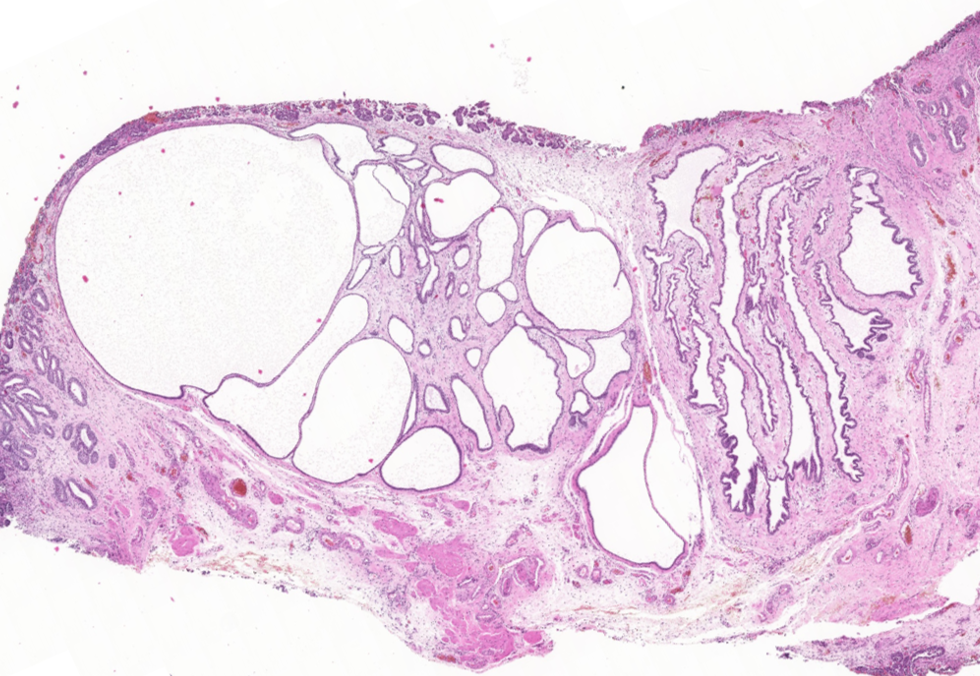

The polyps found in the bladder mucosa consist of a core of proliferative connective tissue covered by surface epithelium. This surface epithelium can form nests of hyperplastic urothelial cells in the lamina propria, known as Brunn’s nests, or undergo metaplasia to a mucus-secreting, glandular epithelial type, leading to a condition called CYSTITIS GLANDULARIS. These resulting polypoid masses may have a broad-based or pedunculated structure, occurring most frequently in the cranioventral bladder wall. Chronic haematuria, often unresponsive to antimicrobial therapy, is a common observation in cases of chronic polypoid cystitis. This bleeding is often associated with the breakdown of polyps, potentially promoting urine retention and bacterial introduction, thus establishing a cyclic pattern of infection, proliferation, and inflammation.

Histologically, our case had in lamina propria, occasionally extending from mucosa, multiple hyperplastic tortuous glands that were often cystic dilated. They were lined by one to multiple layers of uniform cuboidal or columnar epithelial cells, occasionally surrounded by a few layers of urothelial cells. They had no evident atypia. The lamina propria where they were immersed contained a few plasma cells, lymphocytes, neutrophils and rare histiocytes.